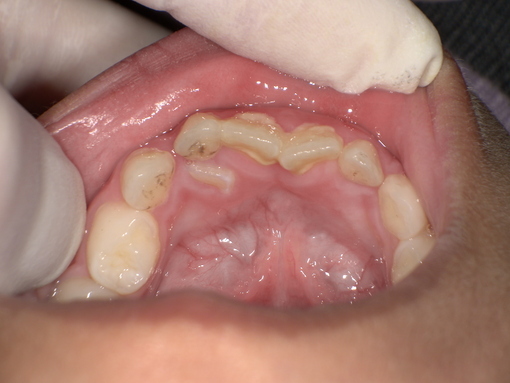

乳歯の抜歯後 After

すでに永久歯が生え始めているため、今の段階で抜歯したほうが、自然に抜けるのを待つよりも歯肉炎のリスクや将来的な歯並びへの影響が少ないことをお伝えし、同意いただきました。

まず痛みを感じにくくする局所麻酔を行い、乳歯を慎重に抜きます。また、患者様ができるだけ不安を感じないよう、お声掛けをしながら治療を進めました。

抜歯後は傷からの出血がしっかりと止まったことを確認し、治療を終了しています。